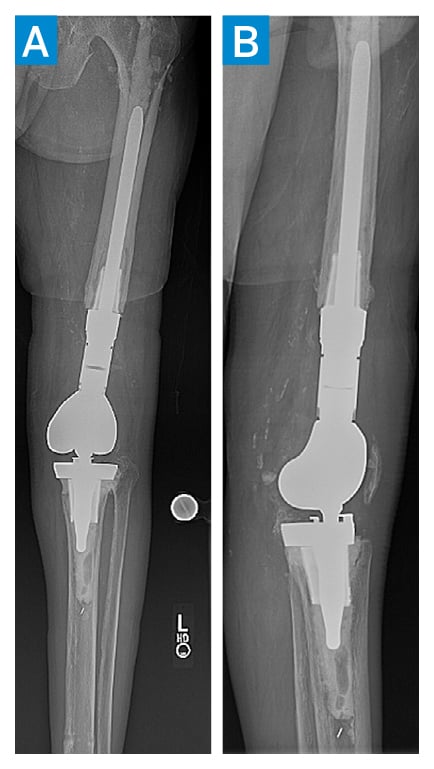

At 6 weeks postoperatively, intraoperative cultures returned negative, and X-ray showed the implants to be in good position, with no complications (Figure 4), and the patient began long-term oral voriconazole therapy.

Figure 4: Plain anteroposterior (A) and lateral (B) radiographs 6 weeks postoperatively, showing implants in good position.